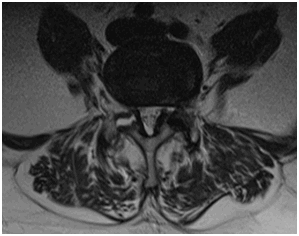

1.Магнитно-резонансная томография

Рис. №6. МРТ поясничного отдела. Спондилолистез L4 позвонка. (А - сагиттальная проекция; Б - аксиальная проекция).

• Спондилолиз бывает сложно увидеть на МР-томограммах:

о Обязательны сагиттальные Т1-ВИ

о КТ используется как подтверждающий метод диагностики мелких переломов

(Справа) Т1-ВИ, сагиттальная проекция: признаки послеоперационного спондилолистеза после проведенной ляминэктомии поясничного отдела позвоночника. Межпозвонковый диск L4-L5 с признаками выраженных дегенеративных изменений, имеет место передний подвывих L4 относительно L5. Обратите внимание на свежий компрессионный перелом верхней замыкательной пластинки L1 позвонка. (Слева) Т2-ВИ, сагиттальная проекция: спондилолистез L4 I степени с признаками дегенерации межпозвонкового диска и сочетанной жировой перестройкой замыкательных пластинок. Также видны признаки дегенерации межостистой связки.

(Справа) Т2-ВИ, сагиттальная проекция: спондилолистез L4 I степени, ставший причиной выраженного фораминального стеноза.